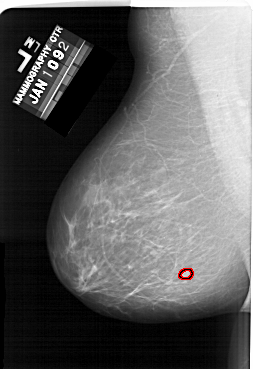

A_1634_1.LEFT_CC

LEFT_CC LINES 6361 PIXELS_PER_LINE 4006 BITS_PER_PIXEL 12 RESOLUTION 43.5 OVERLAY

FILE: A_1634_1.LEFT_CC.OVERLAY

TOTAL_ABNORMALITIES 1

ABNORMALITY 1

LESION_TYPE MASS SHAPE LOBULATED MARGINS MICROLOBULATED

ASSESSMENT 4

SUBTLETY 4

PATHOLOGY BENIGN

TOTAL_OUTLINES 1

BOUNDARY